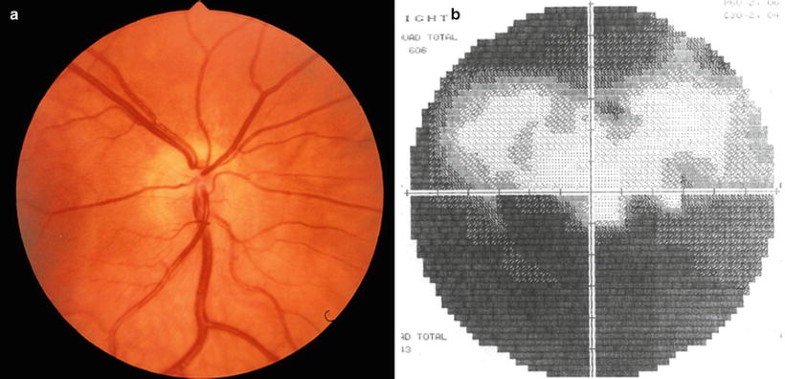

Superior segmental optic hypoplasia. (a) Right optic disc demonstrating abnormal superior entrance of central retinal artery, relative pallor of superior disc, and superior peripapillary halo. Superior nerve fiber layer is absent, while inferior nerve fiber layer is clearly seen. (b) Corresponding Humphrey 60-2 visual field demonstrating nonaltitudinal inferior defect with mild superior constriction. Used, with permission, from Brodsky et al. [65].